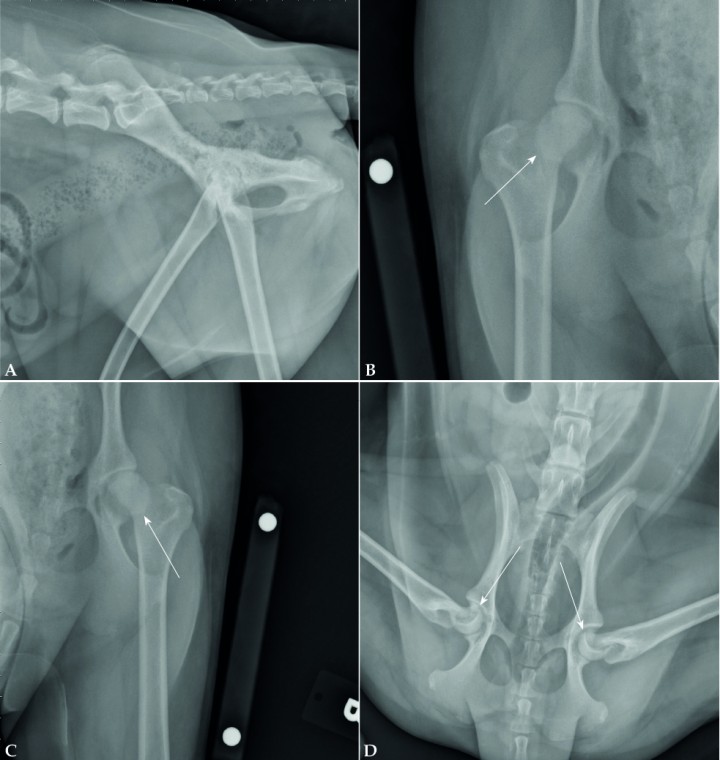

<p>Cuando no se realiza el diagnóstico de las fracturas de las líneas de crecimiento a tiempo, estas pueden tener consecuencias graves, incluso cuando las fracturas afectan a una prominencia ósea como el trocánter mayor del fémur. Radiografías de un cachorro de 6 meses de edad que presenta una no-unión de una fractura de la línea de crecimiento del trocánter mayor. En la proyección mediolateral del fémur (Fig. 8A) se observa esclerosis en la zona de la línea de crecimiento del trocánter mayor y signos de no-unión. En la proyección craneocaudal del fémur (Fig. 8B) se observa una no-unión y cambios degenerativos severos de la articulación de la cadera; estos son debidos a laxitud articular exacerbada por la pérdida de soporte muscular.</p>

Figura 8

Cuando no se realiza el diagnóstico de las fracturas de las líneas de crecimiento a tiempo, estas pueden tener consecuencias graves, incluso cuando las fracturas afectan a una prominencia ósea como el trocánter mayor del fémur. Radiografías de un cachorro de 6 meses de edad que presenta una no-unión de una fractura de la línea de crecimiento del trocánter mayor. En la proyección mediolateral del fémur (Fig. 8A) se observa esclerosis en la zona de la línea de crecimiento del trocánter mayor y signos de no-unión. En la proyección craneocaudal del fémur (Fig. 8B) se observa una no-unión y cambios degenerativos severos de la articulación de la cadera; estos son debidos a laxitud articular exacerbada por la pérdida de soporte muscular.

<p>Comparar radiografías de un miembro con el contralateral es una buena forma de facilitar el diagnóstico de algunas fracturas, aunque podría ser más difícil cuando la fractura es bilateral. Estas radiografías son de un cachorro de 10 meses de edad al que no se le diagnosticó una fractura bilateral de la cabeza femoral. La proyección mediolateral de la pelvis (Fig. 9A) no nos ayudaría en el diagnóstico de esta condición, pero sí para descartar otras patologías. En las proyecciones craneocaudales de cada fémur (Fig. 9B-9C) puede parecer a priori que no existe ningún problema, pero si se observan con detenimiento, se visualiza una radiopacidad en el cuello femoral dando una imagen de una estructura circular que engloba la cabeza femoral (flecha). Esta imagen se debe a la rotación de las cabezas femorales debido a la fractura de la línea de crecimiento. Para mejorar la visualización se realiza una radiografía ventrodorsal con los miembros pelvianos en posición de rana (Fig. 9D). En esta proyección se puede apreciar cómo existe un desplazamiento craneal de la metáfisis en relación con la epífisis (flechas).</p>

Figura 9

Comparar radiografías de un miembro con el contralateral es una buena forma de facilitar el diagnóstico de algunas fracturas, aunque podría ser más difícil cuando la fractura es bilateral. Estas radiografías son de un cachorro de 10 meses de edad al que no se le diagnosticó una fractura bilateral de la cabeza femoral. La proyección mediolateral de la pelvis (Fig. 9A) no nos ayudaría en el diagnóstico de esta condición, pero sí para descartar otras patologías. En las proyecciones craneocaudales de cada fémur (Fig. 9B-9C) puede parecer a priori que no existe ningún problema, pero si se observan con detenimiento, se visualiza una radiopacidad en el cuello femoral dando una imagen de una estructura circular que engloba la cabeza femoral (flecha). Esta imagen se debe a la rotación de las cabezas femorales debido a la fractura de la línea de crecimiento. Para mejorar la visualización se realiza una radiografía ventrodorsal con los miembros pelvianos en posición de rana (Fig. 9D). En esta proyección se puede apreciar cómo existe un desplazamiento craneal de la metáfisis en relación con la epífisis (flechas).